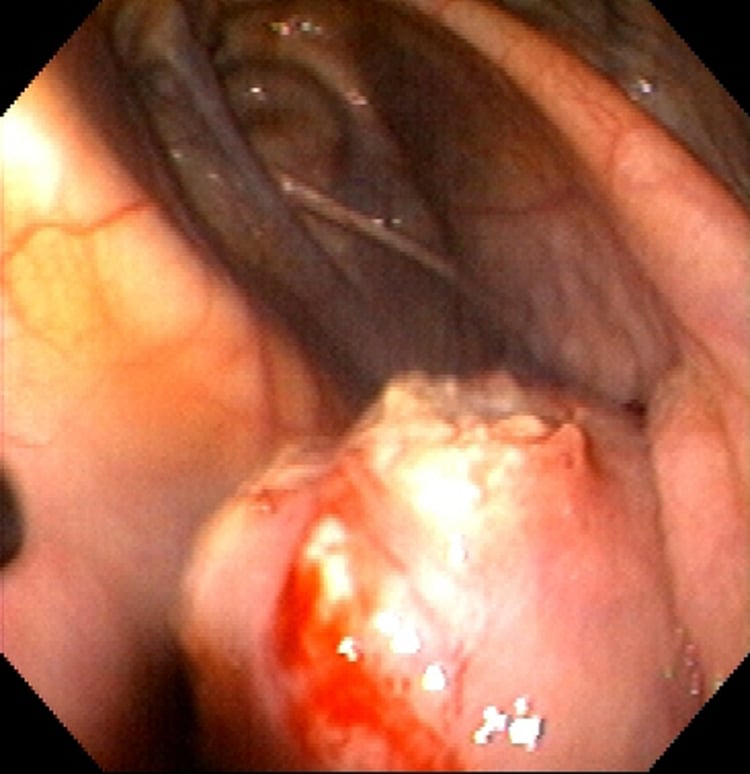

Rotura de un absceso retrofaríngeo por Streptococcus equi, caballo

Imagen endoscópica de un absceso retrofaríngeo por S. equi que se rompe a través del suelo del compartimento medial de la bolsa gutural derecha.

Cortesía de la Dra. Bonnie R. Rush.